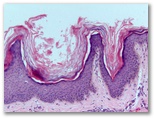

Diagnostico